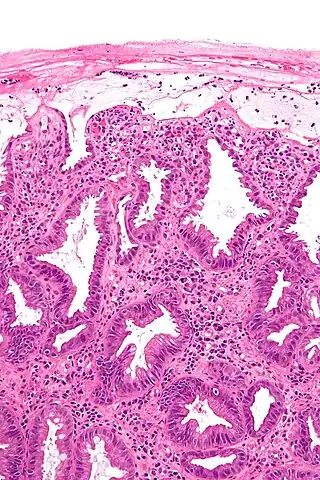

![]() Microfotografía de la mucosa del colon en un caso de colitis isquémica. | ||